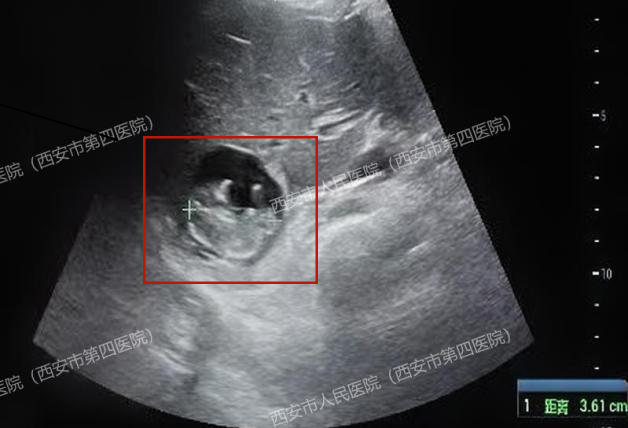

胎儿竟然长在了肝脏上!胎心搏动强劲有力,胎盘雏形也已形成,测量的顶臀径约36mm,估算的孕周近11周了!

肝脏妊娠的诊断需满足最为严格的标准:子宫内无妊娠囊、宫颈管内无妊娠物、双侧输卵管及卵巢正常,以及明确的腹腔内异位妊娠证据。

我院超声医学部与放射科通过高分辨率超声及上下腹部核磁共振(MRI)检查,结合患者血清HCG水平的动态变化,最终排除了子宫及附件妊娠,为后续治疗指明了方向。